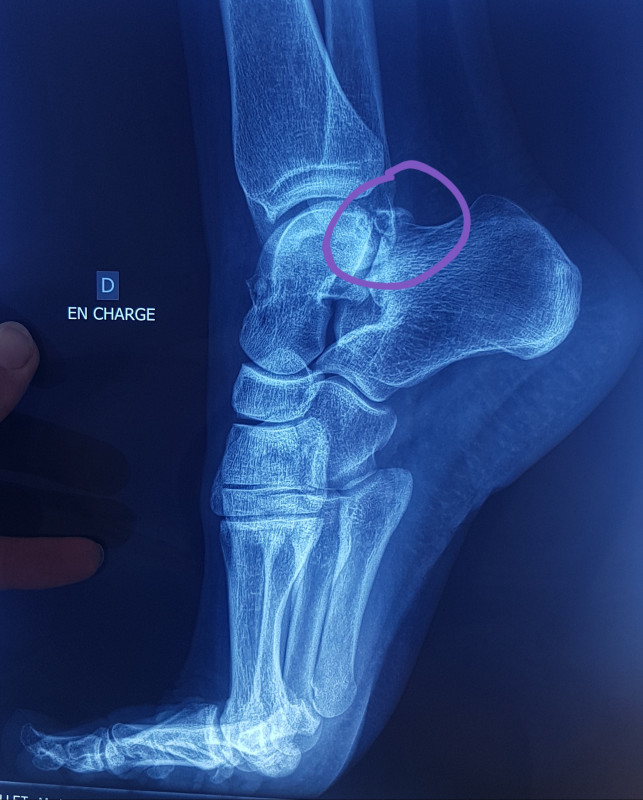

Le problème pour la déformation de Haglund, le tendon étant pris en sandwich entre deux bursites, il me semble que la manip qui est faite rend la convalence vachement longue sans garantie qu'il n'y ait pas de récidive. Il faudrait que je demande des imageries pour voir le niveau d'atteinte